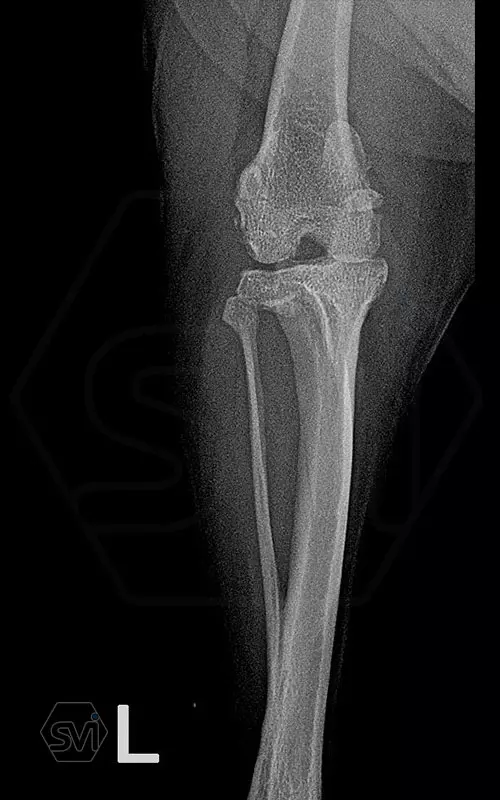

The stifle of a 5.5 kg 10+ old yorkshire terrier dog was operated last week due to a grade 3/4 medial patella-luxation and cranial cruciate ligament rupture. The modified TPLO surgery (TPLO-M) and the recently developed Smartvet TPLO-M mini (terraced) plate are excellent for the simultaneous treatment of lesions.

The next step was an osteotomy with a curved saw using an R12 blade and a Smartvet cordless TPLO saw. Since no JIG is used for the operation, the excised bone piece was grasped with a small pointed condylus forceps (small-spitzige) and adjusted to the desired position by the sterile assistant: that an approx. a 2 mm step should be created. This position was fixed with a 1.0 mm K-wire starting from the proximal end of the tuberositas tibiae. The TPLO-M mini plate was used, with a minimal bend, the proximal piece was curved outward for a better fit. The terraced design of the plate was aligned with the 2.2mm step to the bone. Screw insertion order: proximal middle and cranial holes, then distal middle DCP holes (INTRAOP. PICTURE) The three screws were tensioned continuously and alternately, and the temporaly K-wire was removed, thus providing the opportunity for the displacement to be complete and for the osteotomized tibia to assume the position formed by the plate and for compression to develop between bone surfaces. The other screws were then inserted. In our case, the K-wire was no longer returned. (If there is place and way for it, we can put it back a few tenths of a millimeter thicker than the previous one taken out to relieve the crista tibiae. tibiae may break under the load.)